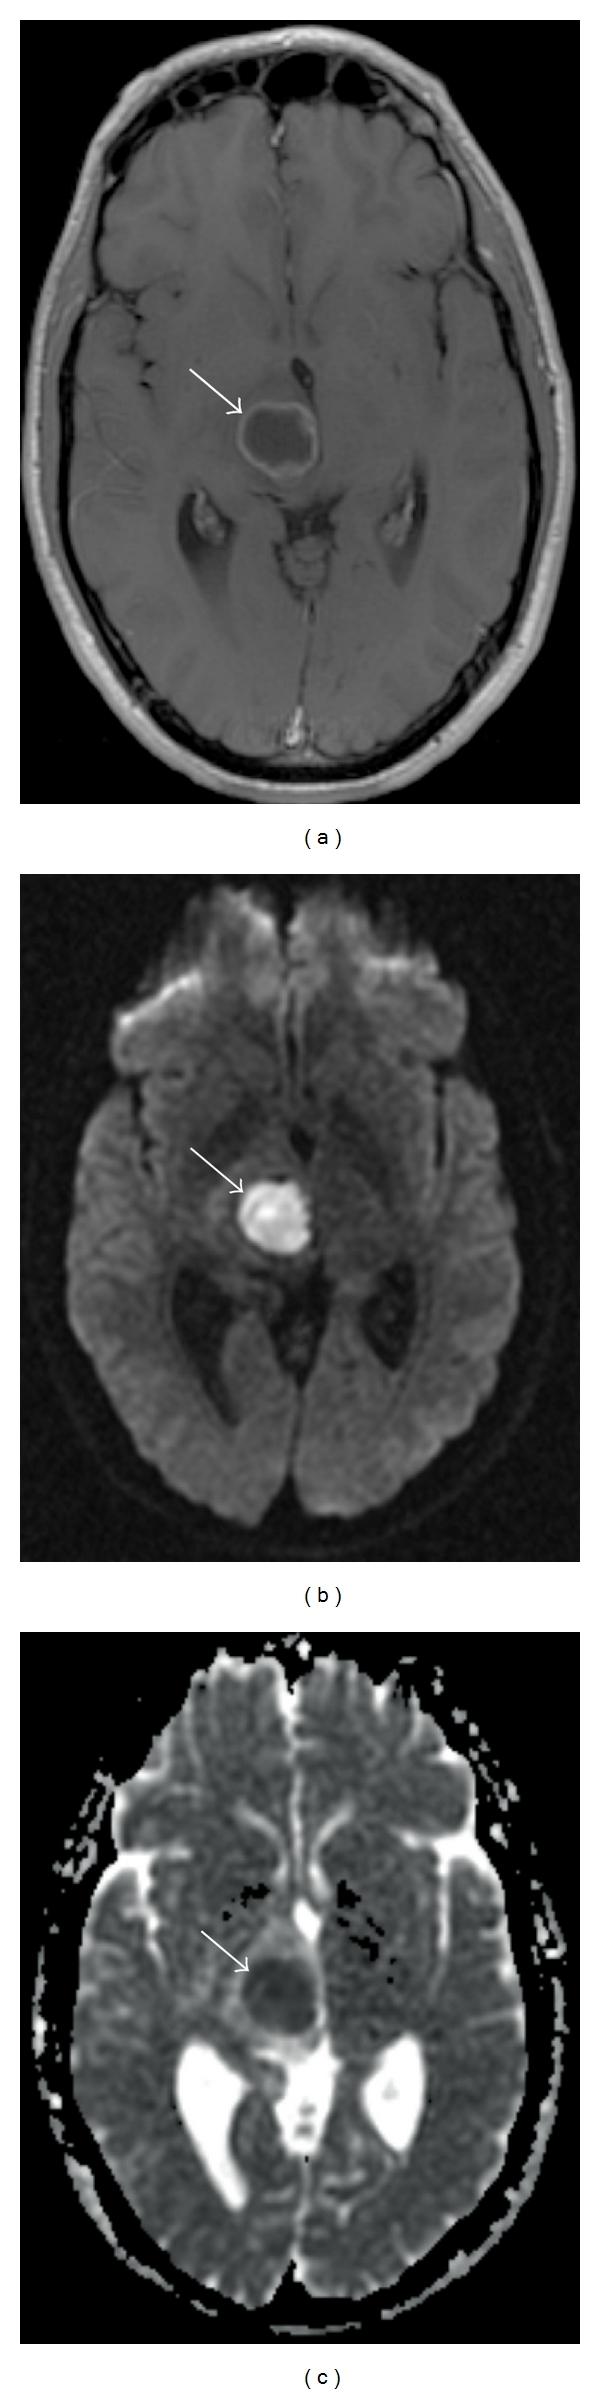

Diffusion MR Imaging of the Brain in Patients with Cancer.

Over the last several years, there has been significant advancement in the molecular characterization of intracranial diseases, particularly cerebral neoplasms. While nuclear medicine technology, including PET/CT, has been at the foreground of exploration, new MR imaging techniques, specifically diffusion-weighted and diffusion tensor imaging, have shown interesting applications towards advancing our understanding of cancer involving the brain. In this paper, we review the fundamentals and basic physics of these techniques, and their applications to patient care for both general diagnostic use and in answering specific questions in selection of patients in terms of expected response to treatment.

在过去几年中,颅内疾病,尤其是脑肿瘤的分子特征研究取得了重大进展。虽然包括PET/CT在内的核医学技术一直处于探索前沿,但新的磁共振成像技术,特别是扩散加权成像和扩散张量成像,在推进我们对脑部癌症的理解方面显示出了有趣的应用。在本文中,我们回顾了这些技术的基本原理和基础物理学,以及它们在患者护理中的应用,包括一般诊断用途以及在回答关于患者对治疗预期反应的特定选择问题方面的应用。